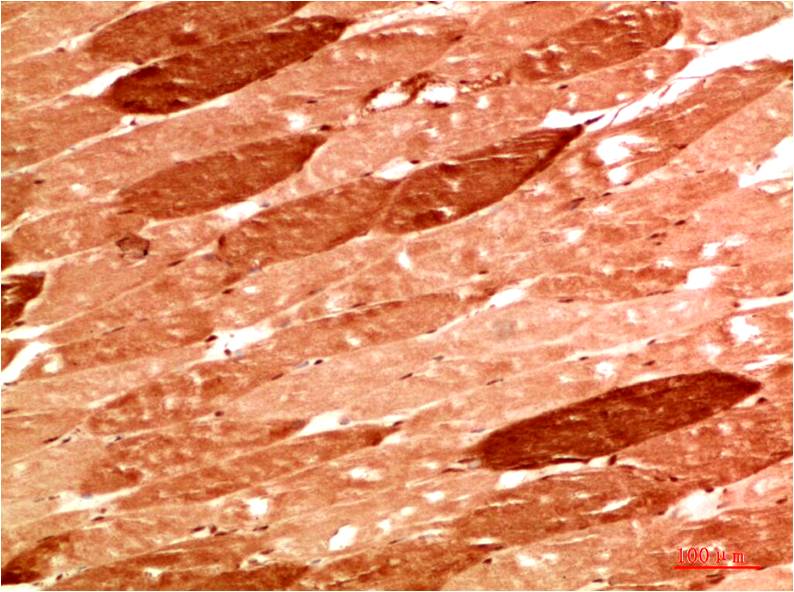

TTR Mouse Monoclonal Antibody(5G9)

Applications :WB, IHC

| Recommended dilutions: | WB 1:1,000-2,000 IHC 1:100-200 |

| Specificity: | The TTR Mouse Monoclonal Antibody can detects endogenous TTR proteins. |